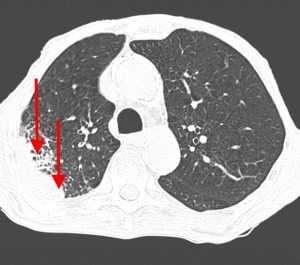

КТ-признаки ТЭЛА. На КТ-ангиограмме, выполненной 53-летнему пациенту, визуализируется внутрипросветный дефект наполнения; имеет место окклюзия артерии переднего базального сегмента нижней доли правого легкого. Определяются также признаки инфаркта правого легкого в виде участка консолидации треугольной формы, широким основанием обращенного к плевре (бугорок Хэмптона).